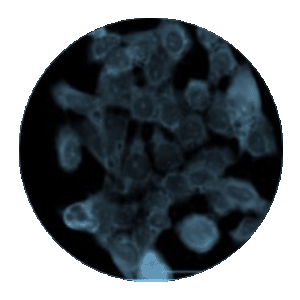

Figure 2A-B. IF of ModDetect Reagent PS05 IF of ModDetect Reagent PS05. Mouse glioma cells derived from C57 black mice were cultured and treated with Oligo Tx drug. After fixation with paraformaldehyde, cells were stained with alpha-tubulin (red) and ModDetect reagent PS05 (green). Reagent PS05 was used at a 1:2000 dilution. Punctate cytoplasmic staining is consistent with endosomal storage of ASO within the cell, as expected for this Oligo Tx drug. Vehicle-only treated cells showed no staining (not shown).